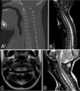

Stenosis of cervical spinal canal

Spinal stenosis is an abnormal narrowing of the spinal canal or neural foramen that results in pressure on the spinal cord or nerve roots. Symptoms may include pain, numbness, or weakness in the arms or legs. [Source: Wikipedia ]